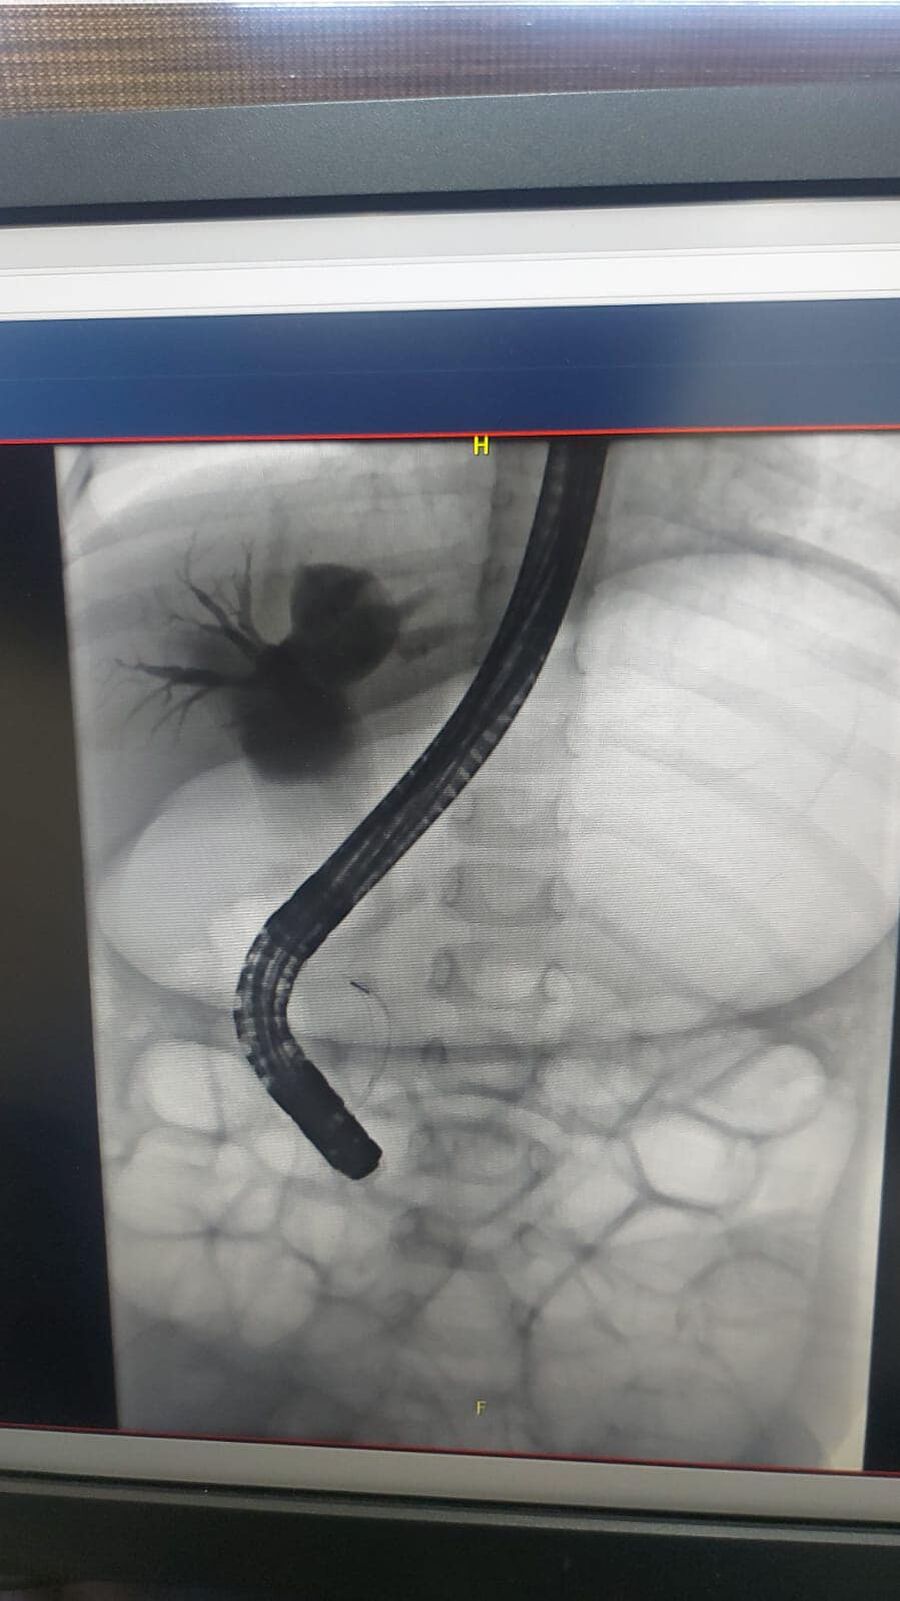

وبين العقيد الطبيب بلال الصمادي أن المريضة كانت تعاني من آلام متكرره بالبطن، حيث تم إستئصال الحصى بالقنوات الصفراويه ووضع الدعامات اللازمه لمنع تكوين حصى اخرى .

وأشار العقيد الطبيب بلال الصمادي أن هذه العملية تكللت بالنجاح بتنظير القنوات الصفراويه وتبين عدم وجود آثار للحصى وتماثلت المريضة بالشفاء التام.